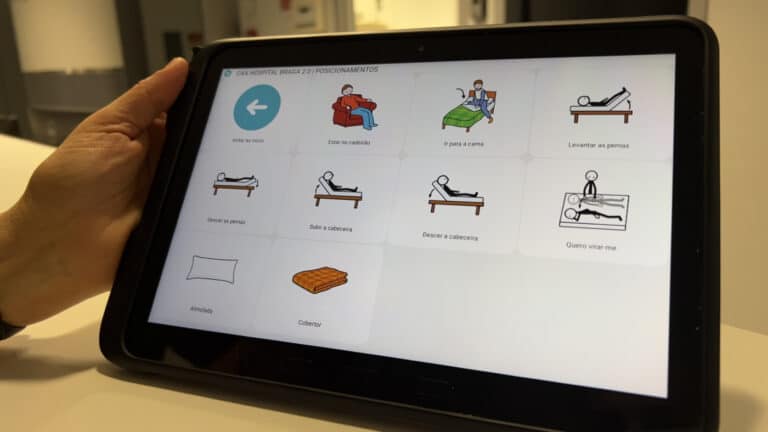

ULS Braga implementa projeto que facilita comunicação entre profissionais e doentes sem voz

Implementadano Hospital de Braga, a aplicação MagicContact permite aos doentes, com dificuldades ou impossibilitados de falar, comunicar de forma simples, intuitiva e eficaz com os profissionais de saúde no serviço de Otorrinolaringologia.

ULS de Braga cria projeto para atender utentes com dificuldades de comunicação

Os utentes podem agora recorrer a uma aplicação, através de tablets. O objetivo é “devolver ao utente a capacidade de participar ativamente nos seus cuidados e manifestar necessidades básicas”.